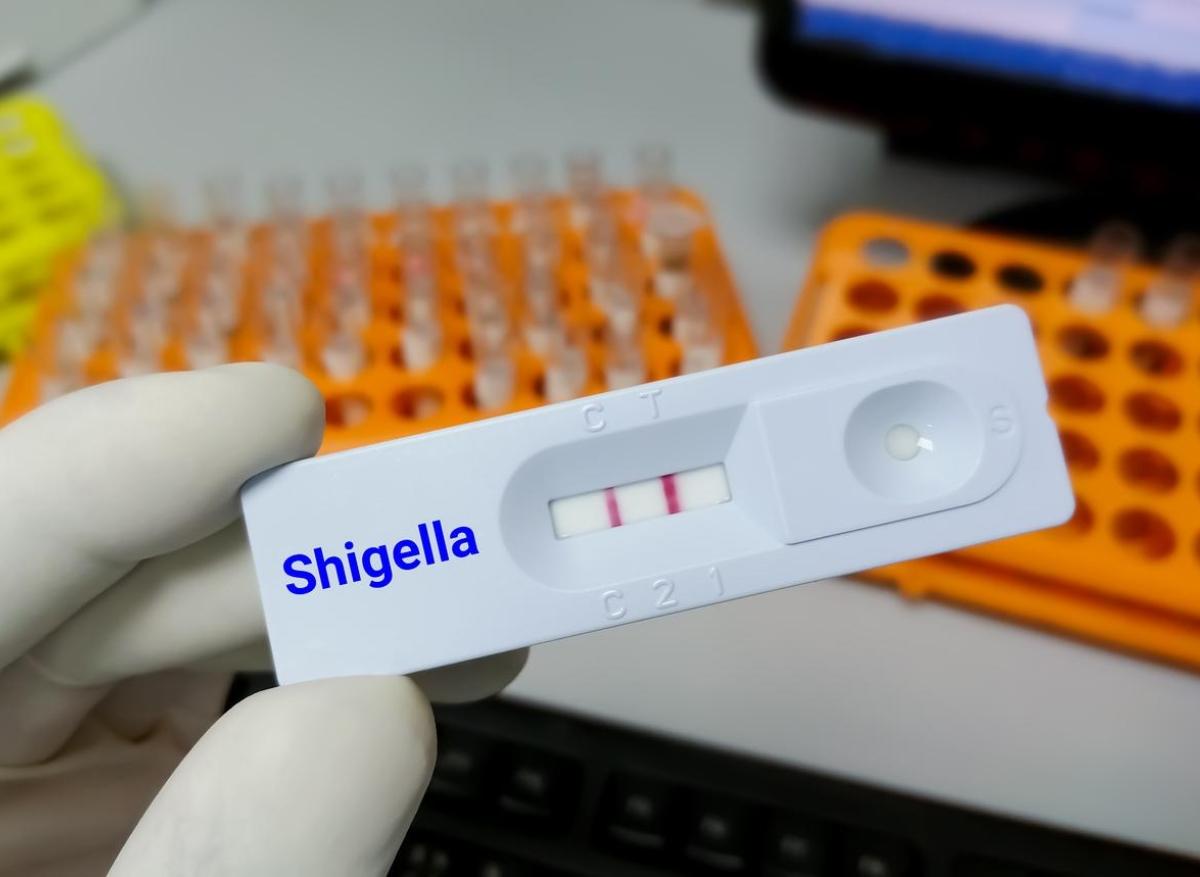

- Md Saiful Islam Khan/istock

En effet, au 16 février 2023, 221 cas de shigellose, principalement à Shigella sonnei, ont été confirmés dans 10 pays européens, le Royaume-Uni et les Etats-Unis. Et 37 cas suspects ont également été détectés. Tous revenaient du Cap Vert.

Une bactérie résistante

Côté traitement, la principale souche retrouvée, Shigella sonnei, oriente vers une résistance au triméthoprime et à la streptomycine. Toutefois, des cas de multirésistance ont déjà été détectés.